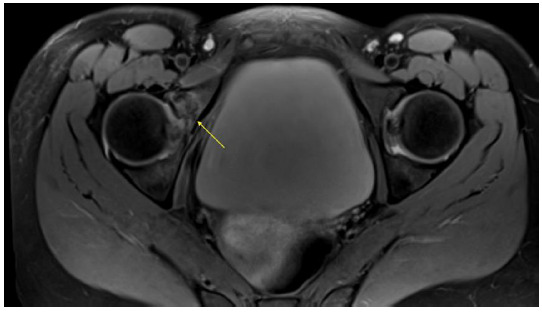

近几十年来,自行车作为一种交通工具和一项竞技运动的参与稳步增加。由跌落和碰撞引起的创伤性损伤发生的相对频繁。髋部和骨盆骨折并不常见,迄今为止没有研究报道其在这项运动中的确切发生率。髋臼特异性损伤的报道甚至更少。我们提出了四个病例,突出了骑自行车者髋臼骨折的隐伏性,并记录了他们的管理和恢复。从自行车上直接跌落到髋侧部导致髋臼骨折的数量相对较高。其中许多可能因x线平片未见发现而被遗漏。因此,在治疗与骑行相关的创伤性损伤时,高度怀疑髋部和骨盆骨折是很重要的。

Cycling participation as a medium of transport and as a competitive sport has steadily increased in recent decades. Traumatic injuries secondary to falls and collisions occur relatively frequently. Fractures of the hip and pelvis are uncommon with no studies to date reporting their exact incidence in this sport. Injuries specific to the acetabulum are reported even less frequently. We present four cases that highlight the insidious nature of acetabular fractures in cyclists and document their management and recovery. The number of acetabular fractures following falls from bicycles directly onto the lateral hip result in a relatively high number of fractures. Many of these may be missed due to the absence of findings on plain x-ray imaging.It is therefore important to have a high index of suspicion for hip and pelvis fractures when treating cycling related traumatic injuries.